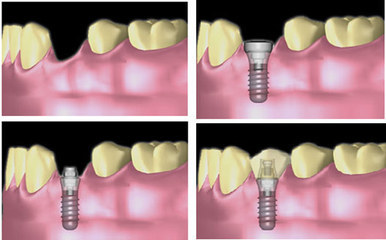

随着人们对生活质量要求的不断提高,越来越多患有牙齿缺失的人们开始选择更加安全和具有良好效果的种植牙来修复口中缺牙。近年出现的微创即刻种植牙技术,短短几分钟内让缺牙重生,具有创伤小、治疗周期短、术后恢复快、使用效果好等特点,堪称牙齿修复技术的一大飞跃,深受众多中老年缺牙患者的青睐。

种牙错过黄金期代价高

缺牙时间越久,数目越多,修复效果越差。牙槽骨是支撑牙齿的关键,天然牙通过牙根将咀嚼力传递至牙槽骨,刺激牙槽骨的生长;长期缺牙、戴假牙失去了咀嚼的生理刺激,易出现牙槽骨流失,引发接二连三掉牙,对全身健康影响很大。

当牙槽骨严重萎缩时种牙,就需要先植骨,这无疑增加了手术难度,延长了治疗时间,增加了手术费用,所以一旦出现牙缺失,应及时修复及时治疗。

无需再等6个月 2小时即刻舒适化"长"牙

种植牙口内无异物感,能恢复90%以上的咀嚼率,外观、功能与真牙一样,使人忘记假牙的存在。美国口腔颌面外科医生协会报告,种植牙的20年成功率高达95-97%,如果维护得当可使用。可传统种植牙需等待6个月,很多人嫌麻烦望而却步。

康贝佳微创即刻种植牙技术全程几乎无疼痛感,利用口腔CT提供准确的数据支持,按照事先设计好的位置、角度、深度将纯钛"生态牙根"植入牙槽骨,修复时间从传统的6个月缩短至更快2小时,欢迎大连市民报名观摩此次技术直播。